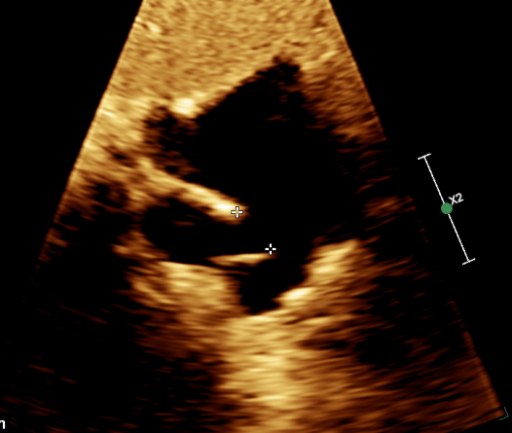

图 3 剑下双房切面显示房间隔回声失落约 17mm ,上腔静脉端无边,距下腔静脉约 30mm

图 5 右上肺静脉进入上腔静脉-右房入口处